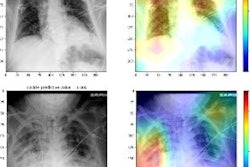

(Panel A) Artificial intelligence (AI) helped detect right upper lobe nodules (arrowheads) for three junior (J) radiologists, as well as improved the confidence score for one senior (S) radiologist (score > 5 implies positive finding). Likewise, AI-aided interpretation led to detection of missed right upper lobe nodules (arrowheads) for the radiograph in panel B for two junior radiologists and improved confidence of two junior radiologists. Image courtesy of JAMA Open Network.In addition, junior radiologists saw greater improvement in sensitivity for nodule detection with AI-aided interpretation as compared with their senior counterparts (12% vs. 9%), while senior radiologists experienced similar improvement in specificity (4%) as compared with junior radiologists (4%).